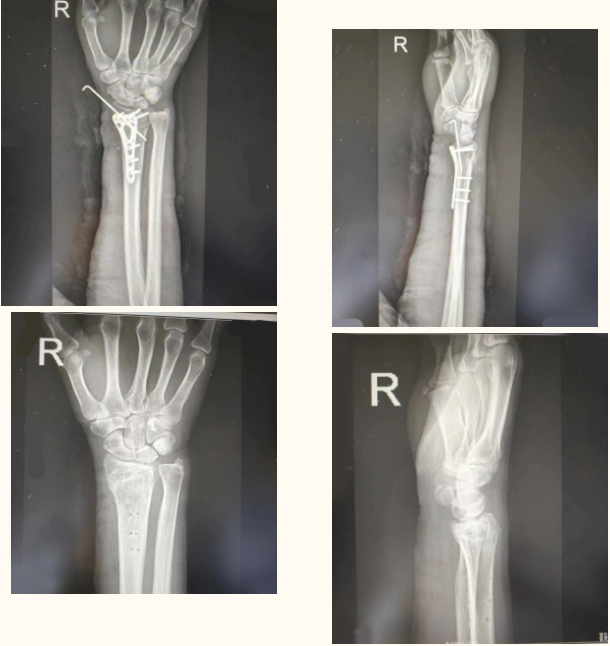

对于广大患者来说,内固定物取出以后才能算是骨折治疗结束了;骨科患者在接受内固定手术前后,大部分患者问得最多的一个问题就是:骨头长好以后,钢板要不要取,能不能不取?

儿童由于骨骼系统正在发育,放在体内的内固定可能会影响骨骼的发育和形态,还是建议去除。年轻人活动量大,谁也难以保证在骨折愈合后几十年里不再受伤,而一旦受伤,因为钢板存在应力遮挡问题,以及在钢板与骨交界位置存在强度不一致,受伤以后很容易出现钢板周围骨折、钢板断裂等问题。

4、内固定放置在体内时间越长,钢板和螺钉越容易出现问题,且时间越长,骨骼生长过程中的骨痂就可能把钢板包裹,取出过程中需要铲除钢板、螺钉表面骨痂才能显露出钢板,另外螺钉被骨痂包裹、冷焊接等非常容易出现滑丝难以取出等并发症。再加上国内的器械公司众多且多不长久,5年以后当时提供钢板的器械公司已经倒闭或配套器械早已更新换代淘汰不用了,不能提供配套取出器械,导致内固定无法取出,甚至会“白挨一刀”,最终产生医患纠纷,造成不必要的麻烦。(供稿:创伤外科 蔡树衡 部分图片来源于封面)